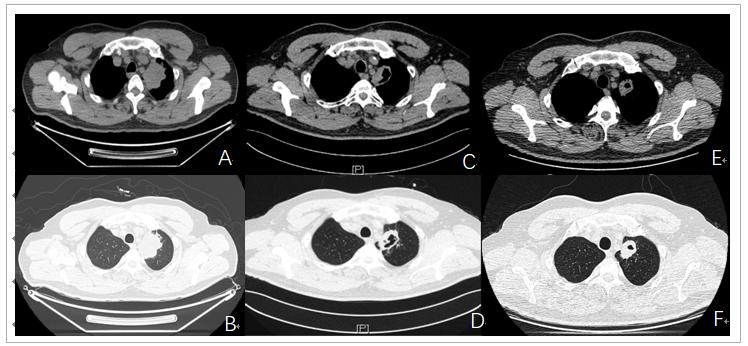

患者张某,男性,49岁,主因“间断左胸背痛伴左上肢麻木肿胀2个月”于2019年3月25日入院,入院查体神清,双肺呼吸音清,心、腹未见明显异常。实验室检查:血常规,肝肾功能基本正常,肿瘤标志物:细胞角蛋白19片段(Cyfra21-1) 6.42ug/L(正常0~3.3ug/L),其余肺部肿瘤标志物均在正常范围。行PET-CT:左肺尖可见软组织肿物影,密度欠均,CT值28-40Hu,增强后呈不均匀强化,CT值33-95Hu,边缘毛糙,牵拉临近胸膜,PET显像可见异常放射性农具,SUV值15.2,大小约5.1cm*4.1cm*4.1cm,周围可见多发斑片,条索及结节样影,考虑为周围性肺癌,临近胸膜受累。临床分期为T3N0M0,ⅡB期(图1A-B)于2019年4月4日进行CT引导下左肺上叶肿物穿刺,穿刺病理结果为:低分化非小细胞癌,结合免疫组化符合低分化鳞状细胞癌。免疫表型P40(+),CK5/6(-),CK7(+),TTF-1(-)。未见明显化疗禁忌症,分别于4月14日,5月8日,5月27日及6月19日分别行四周期新辅助化疗联合免疫治疗,具体用药方案为三周方案:紫杉醇(脂质体)270mg d1,卡铂600mg d1,纳武利尤单抗360mg d1。患者化疗反应不著,I度消化道反应及骨髓抑制。四周期治疗结束后肿瘤标志物Cyfra21-1降为3.31ug/L, 1周复查胸CT(28/6/19)提示:左肺上叶肿物较前缩小(3.6cm*2.5cm),其内实性成分略增大,疗效评价PR(图1C-F)。自第4周期新辅助治疗结束后患者逐渐出现咳嗽,胸闷,低热症状,胸CT提示双肺胸膜下多发实变浸润,考虑免疫性肺炎可能(图2A),予甲泼尼龙冲击(160mg/d)3天,而后逐渐减量至40mg,共2周,同时予头孢哌酮舒巴坦对症治疗,2周后改为泼尼松15mg口服,患者症状明显好转,复查胸CT左下肺斑片影较前吸收(图2B)。后患者充分评估后于2019年10月17日行达芬奇机器人辅助下胸腔镜左上肺切除+区域淋巴结清扫术,手术过程顺利,术中未见明显胸膜受侵,术后病理提示:左上肺低分化癌,结合免疫组化考虑大细胞癌伴鳞状细胞癌分化,并伴大量坏死,送检壁层胸膜(-),区域淋巴结未见癌转移,病理分期T2bN0M0ⅡA期。术后患者恢复良好,后患者先后行3周期术后辅助化疗,三周方案,具体为紫杉醇(脂质体)240mg d1,卡铂500mg d1。目前定期复查密切随诊,状态良好,无复发及转移征象。

图1 患者胸部CT提示肿物情况(A-B)基线期(3/29/19);(C-D)新辅助治疗2周期后复查(27/5/19);(E-F)新辅助治疗4周期后2周(28/6/19)